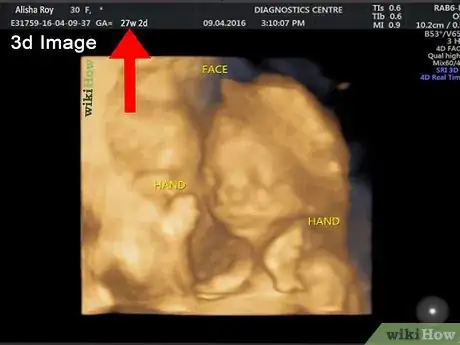

4Consider a 3D or 4D ultrasound. If you are interested in seeing more details of your baby than a traditional ultrasound can provide, then you may want to ask your doctor about a 3D ultrasound. A 3D ultrasound can show your baby’s facial features and it may even be able to detect certain defects, such as a cleft lip and palate.[10] A 4D ultrasound uses the same imaging as a 3D scan, but a 4D scan makes a short video recording of your baby in the womb.[11]

- If you want to have a 3D or 4D ultrasound, the best time to do so is between 26 to 30 weeks.

- Keep in mind that these scans can be quite expensive and may not be covered by your insurance unless there is a medical reason to have one done, such as to investigate an abnormality.